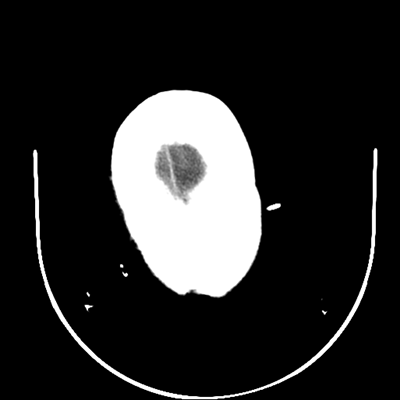

The patient goes down to CT. The following images are obtained. The subdural fluid collection is stable, as is the ventricular caliber.

NCHCT

Starting with the non-contrast head CT, we can appreciate that there's actually not much residual subarachnoid blood at all; it's essentially all resorbed already (and cleared through the EVD). The ventricular caliber is stable. With the CTA head (for convenience's sake, the MIPs were shown), it's subtle, but we can see that the PCAs on each side are not as smooth and regular. The right MCA, starting at the bifurcation, also becomes narrower. This is [radiographic] vasospasm. Now, looking at the CT perfusion-- specifically, the Tmax (MTT) map that were selected-- there's clearly some abnormality within the bilateral cerebellar hemispheres and occipital lobes. Not a lot, but it's there. Delving further into this map, we can appreciate that the areas of abnormality are mainly green, signifying that these areas have Tmax > 6 seconds. This is the threshold that is specific, not sensitive, for vasospasm.